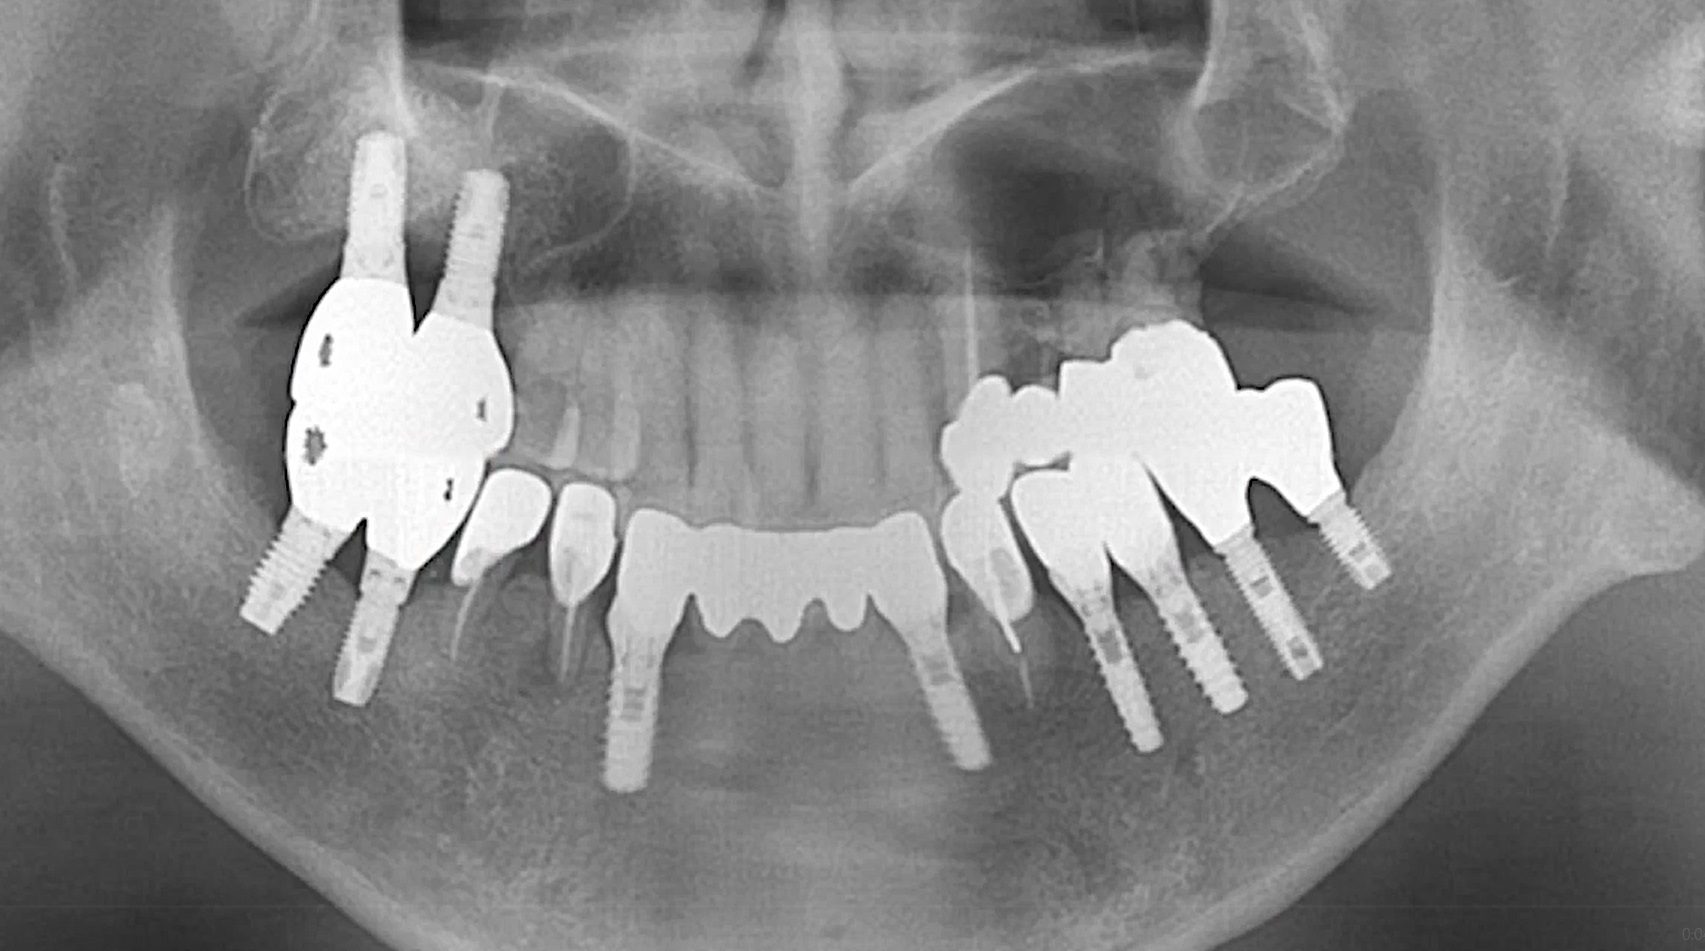

Dr Segin Chandran,Single replacement,Bone regeneration,Digital Guided Surgery,Maxillary Posterior,#25,Immediate Placement,Sinus Elevation,Guided surgery,AnyRidge,R2GATE Guide,R2GATE Surgical Kit(AnyRidge),MICA,Crestal elevation,Minimally invasive,Video